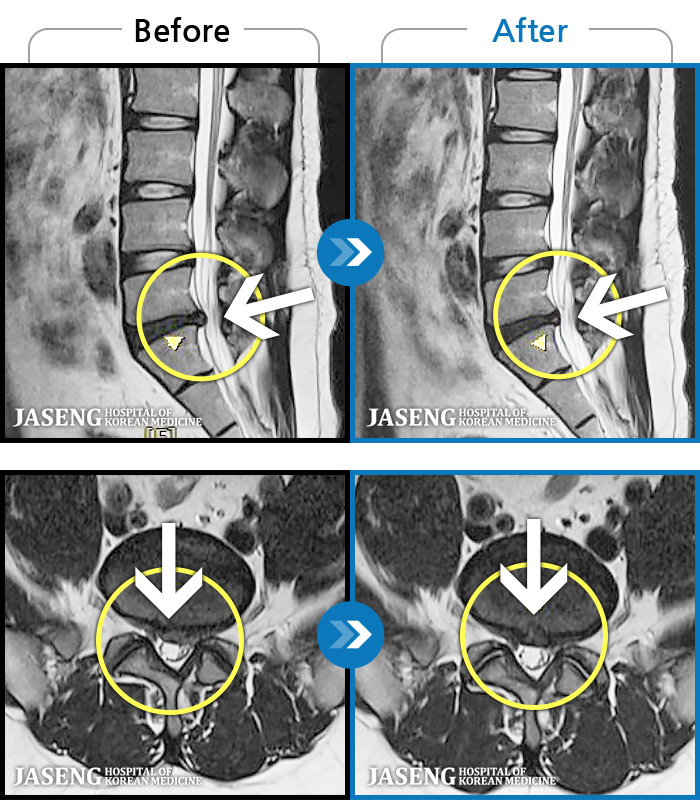

[뱸] 19.11.28~25.05.06